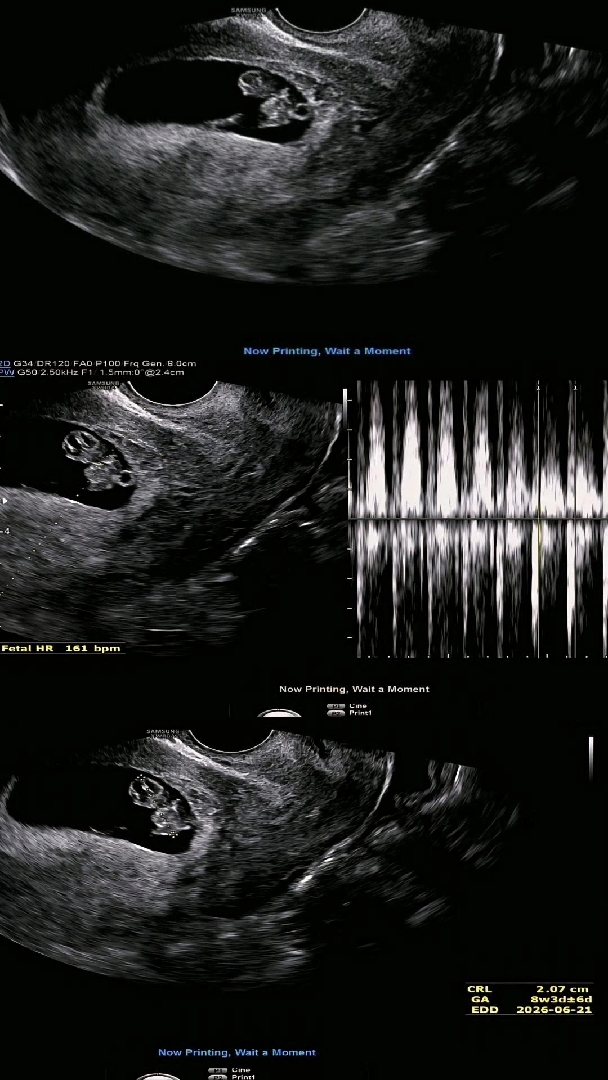

8주 4일 젤리곰 보고왔어요!

아침에 소변보고 나서 갈색혈이 3방울 정도 떨어져서 놀래서 후다닥 병원갔는데 다행히 아기는 괜찮았는데 출혈은 일주일간 질정넣어보자고 하셨어요~ 젤리곰 보고왔는데 도치맘인건지 왤케 구여운지 입덧 심해서 약도 타왔는데 초음파보니 힘이 납니다! 제발 건강하게 딱 붙어있자~ 성별 얼른 알고싶어용 ㅎㅎ